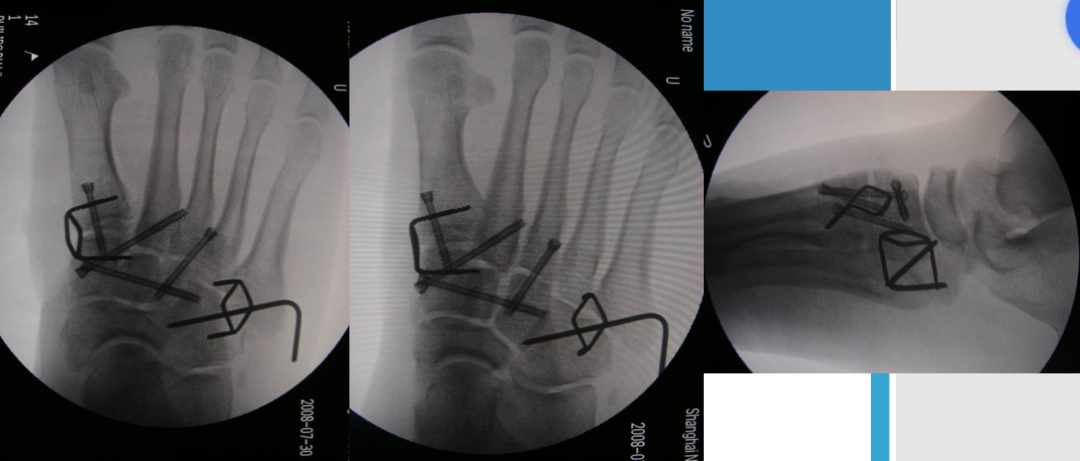

根据三柱理论1、首先复位内侧柱并临时固定 2、再复位固定中间柱3、如外侧柱移位可能需双切口

手术从第一跖骨和内侧楔骨开始。首先直视下复位该关节,评价楔骨之间的稳定性,关节囊通常撕裂,但仍然需要掀开以充分显露关节,清除关节内的软组织和软骨碎片内侧柱稳定后,开始处理第二跖骨和中间楔骨。点式复位钳由第二跖骨基底部外侧远端斜向内侧楔骨内侧面的近端夹持,注意避免第二跖骨向下移位,发生复位不良。

若楔间关节仍不稳,可使用楔骨间螺钉;固定内侧两跖骨后,通常第三跖骨已经足够稳定,若仍未复位,可以参考第一跖骨固定方法固定。通过第二切口固定第4、5跖骨。可以使用克氏针固定。

Lisfranc损伤骨折复位标准:1、C形臂透视显示正、侧、斜位均为正常解剖复位2、如复位后第1、2跖骨基底间隙和内、中楔骨间隙<2mm,跖跗骨轴线<15°为近解剖复位,可以接受,超过这个范围的移位则无法接受3、复位好后,沿第一跖骨轴线向内侧楔骨逆行拧入一枚4.0mm皮质骨螺钉。螺钉由关节远侧1.5-2.0cm处进入,平行于足底或略向跖侧。

4、从内侧楔骨向第二跖骨置入一枚螺钉,重建韧带。螺钉自内侧楔骨近端的背侧置入,指向第二跖骨背侧皮质的下方,螺钉应通过4层皮质,确保对第二跖骨的双皮质固定

单纯克氏针、螺钉固定不适用于粉碎性骨折,特别是合并短缩的骨折,后期易导致畸形愈合。克氏针外固定架联合固定可对内侧柱进行支撑复位;对于内侧柱粉碎骨折患者,微型外固定架有一定的优势。